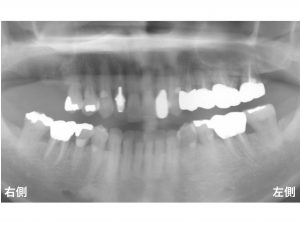

以下が初診時です。

上顎右側の奥歯が2歯 欠損しています。

このような場合、

何本のインプラントが必要なのでしょうか?

欠損は、2歯ありますが、

本症例の患者様は、

おくまで噛めるようにするため、

2本のインプラント治療をご希望されました。

以下が治療後です。